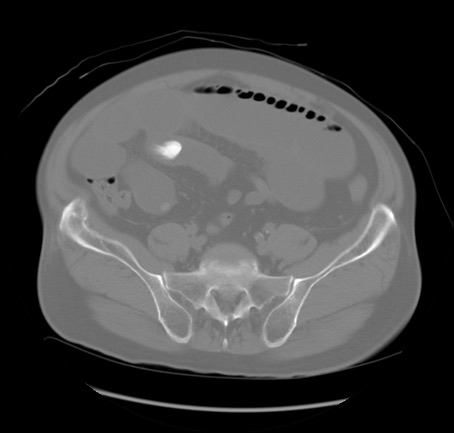

症例20(横断像)

【症例】 60歳代男性

【主訴】 腹部膨満、嘔吐

【現病歴】5日前頃より倦怠感を認め食事量減少し4日前の朝嘔吐、食事摂取困難となった。 3日前近医受診し点滴施行され整腸剤などを処方された。 当日他院を受診し、腹部膨満著明、炎症反応の上昇(CRP10.8、WBC11200)あり、紹介受診となる。

【身体所見】 意識JCS1 受け答えがはっきりしないBP 111/57mHg、 P 67bpm、、BT35.2°C、SpO2 97%(RA)、 腹部:膨隆、打診で鼓音あり、全体的に圧痛有り、腸蠕動音(-)、反跳痛ははっきりせず。

【データ】WBC 11400、CRP 14.20